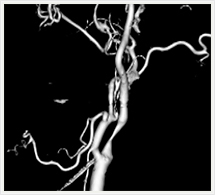

画像紹介(頭頚部血管編)

画像は、頚動脈の狭窄部分に“ステント”と呼ばれる金属性の網状の筒を留置して、血管を正常径まで拡張させる手術です。この治療は、内膜剥離術と比較して非侵襲的であり、高齢者やいろいろな合併症を持った方にも負担を少なくして行うことができます。術後の安静期間や入院期間も短いのが特徴です。